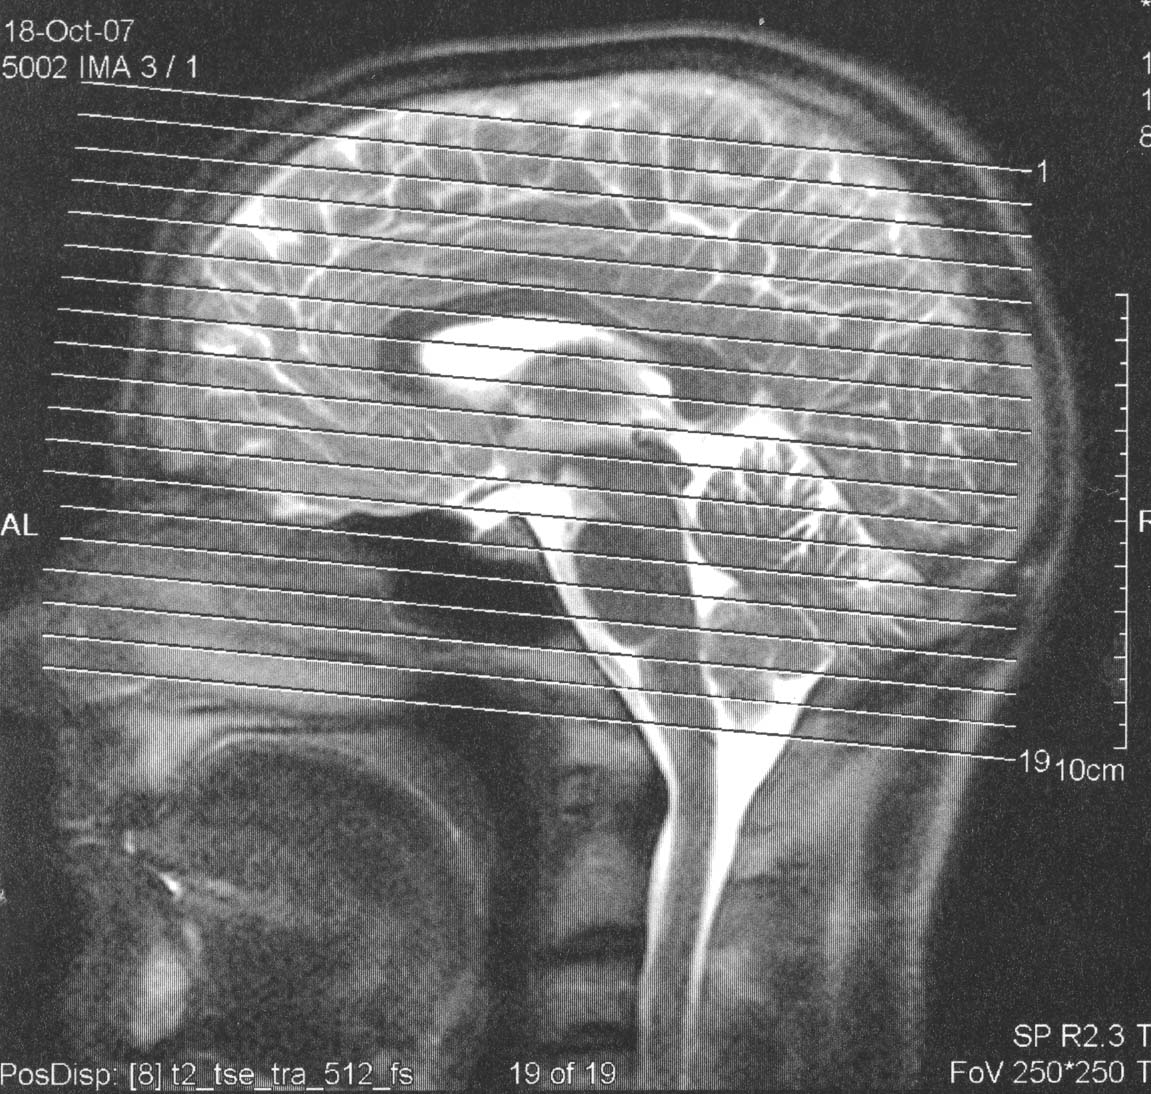

Ah ja, habe heute mal meine MRT Bilder auf den Scanner gelegt. So schaut mein Holzkopf von innen aus: